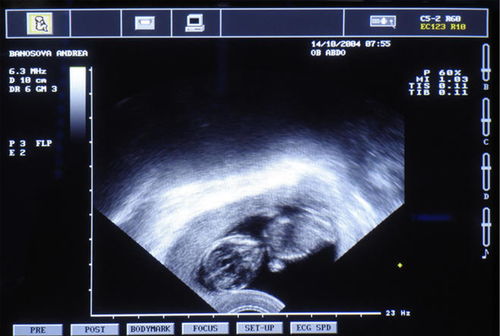

陰式彩超使用的是高頻探頭,功能較強(qiáng),主要是用于婦科疾病的檢查,使用此技術(shù)可監(jiān)測卵巢卵泡的發(fā)育情況,可清晰觀察盆腔器官及細(xì)小病變,并能探測到子宮、卵巢血流情況。此外,也可對早孕、早期異位妊娠、子宮卵巢腫瘤病變、早期子宮內(nèi)膜病變、盆腔膿腫、炎性腫塊等病變進(jìn)行診斷,而且檢查結(jié)果也較準(zhǔn)確。

由于陰式彩超需要通過陰道放探頭檢查,所以過往沒有過性生活的病人是絕對不能使用這種方法的,一般在做陰式彩超之前醫(yī)生都會先詢問病人這個方面的情況。另外,陰道出血較多的病人,比如正在月經(jīng)期、陰道不規(guī)則出血或有陰道炎癥的患者也不適宜做陰式彩超,因?yàn)榭赡軙懈腥?、交叉?zhèn)魅镜奈kU。還有,一般來說做陰式彩超較好是在月經(jīng)干凈后的三到四天比較適宜。